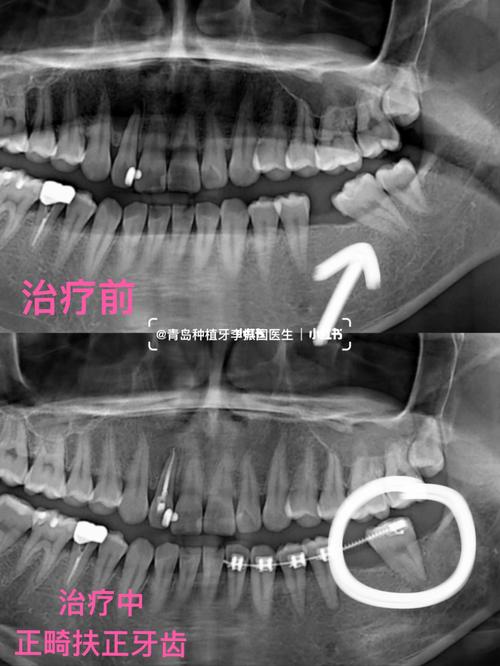

0mmx10mm植体_正畸_发炎_种植牙

根管治疗后不及时做牙冠导致牙齿劈裂种植牙_根管治疗

感染是种植牙失败的主要原因,若是骨量不够的患者,必须在植牙前填充